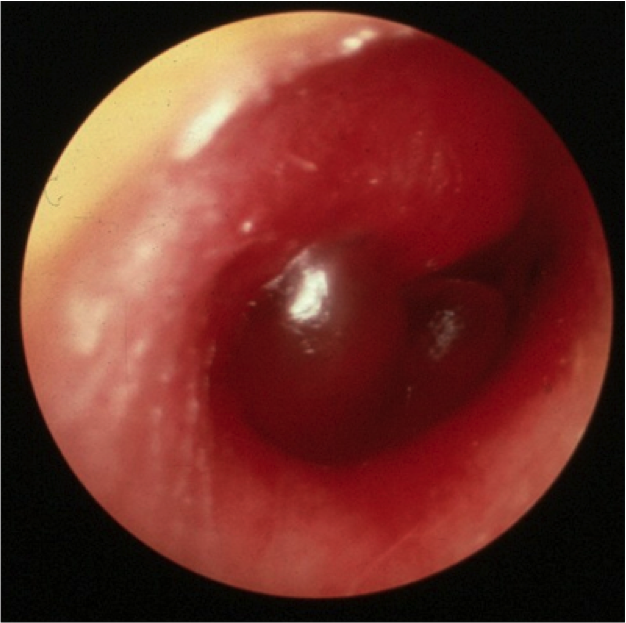

Describe exam findings with AOM.

Hx: otalgia, w/ or w/o fever, pain,

PE: Retracted or bulging TM w/ erythema